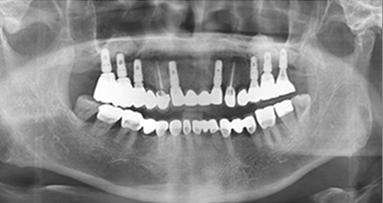

治療です。 前後写真

入れ歯の不快感を解消し、全顎インプラントを完成させます。

自然な機能と審美性の両方を満たす結果です。